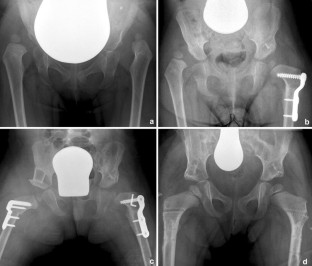

Twenty-seven children (3.4±2.0 years), including 33 hips with developmental hip dysplasia (DDH) and dislocation of the hip (Tönnis grade 1 to 4), who underwent hip reconstruction (Dega acetabuloplasty, varisation-derotation osteotomy and facultative open reduction) were retrospectively included in this study. Postoperatively the patients were placed in an individual foam shell with 30 degrees of hip abduction, hip extension, and neutral rotation. Early mobilization physiotherapy was performed within the first few days after the surgery under epidural anaesthesia. Full weight bearing was allowed after 3–4 weeks. All children received a clinical examination and radiographic evaluation before and after surgical intervention. The follow-up period was 12.3±2.9 months.

On average, the postoperative acetabular index decreased significantly from 36.9 to 21.7 degrees and the center-edge angle increased from 9.9 to 28.6 degrees. All hips had reached Tönnis grade 1 at the time of the last follow-up. No complications such as dislocation of the bone wedge, avascular necrosis of the acetabulum or femur, lack of non-union, or nerve injury, were reported.